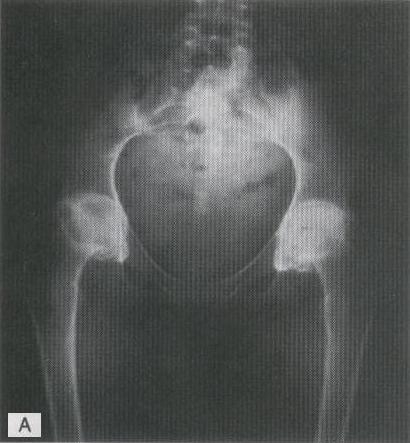

ARTRITIS REUMATOIDEA BILATERAL DE LAS CADERAS